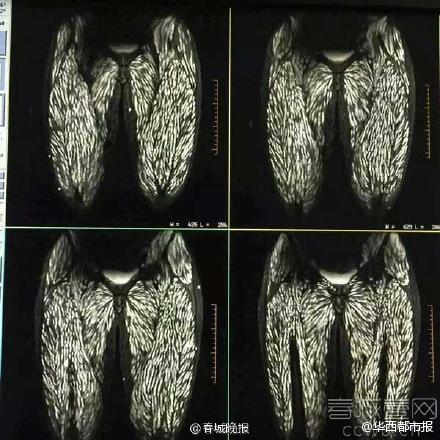

密集恐惧症慎入男子吃生鱼片体内长满寄生虫